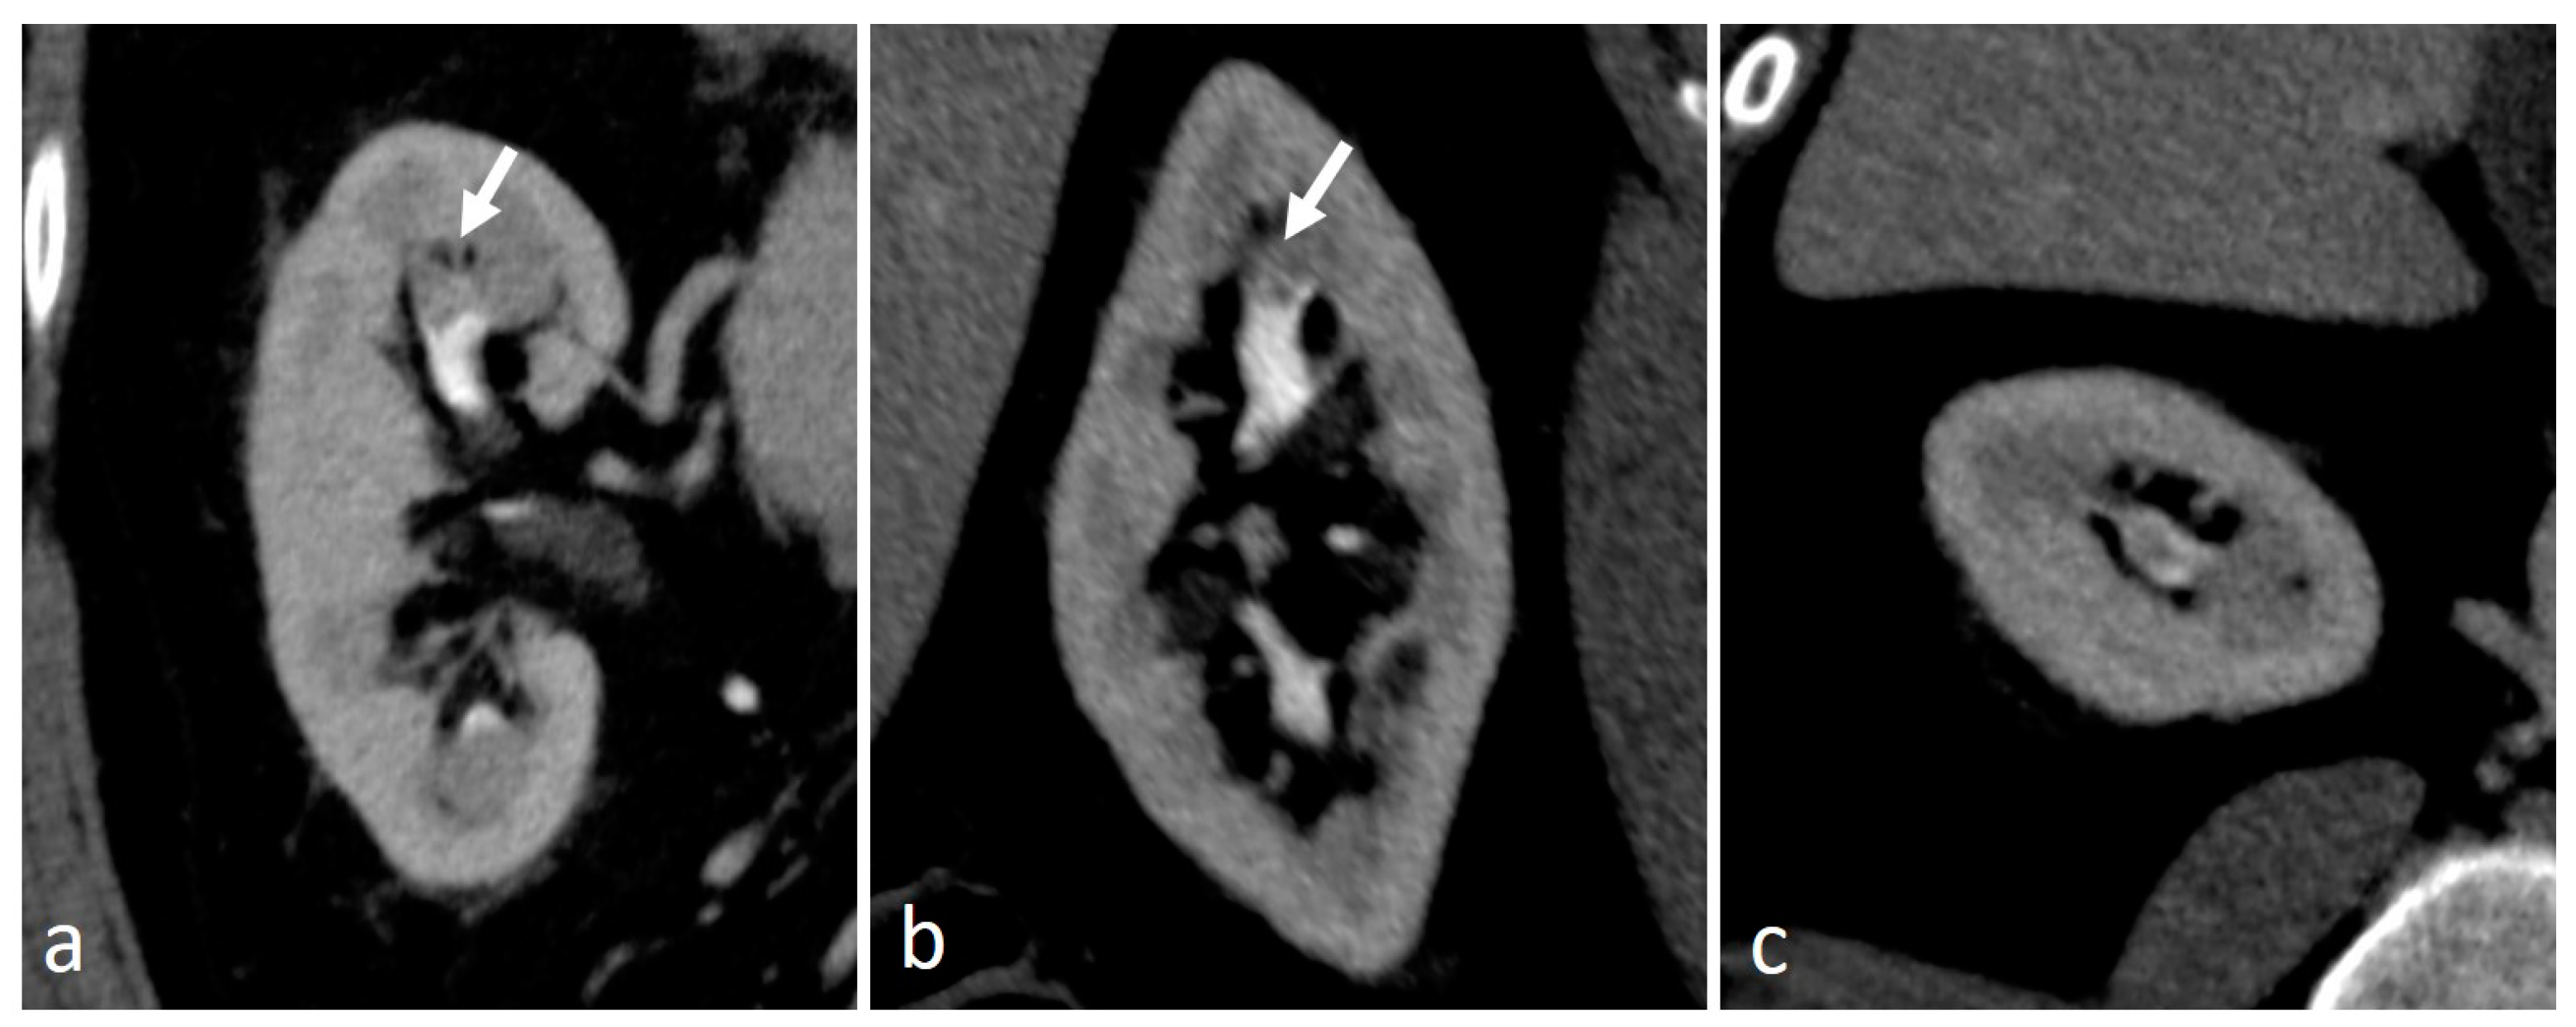

4.8. Urogenital Tuberculosis

4.9. Fibroepithelial Polyp